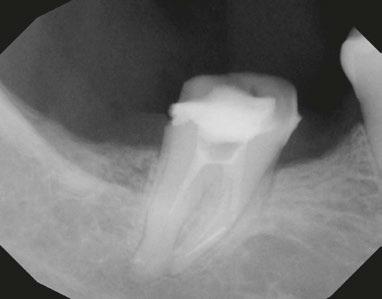

Case 2: This is a 23-year-old male that presented with a constant dull ache in his tooth. Tooth No. 30 tested necrotic with SAP. The CBCT did not reveal any odd anatomy and appeared to be fairly straight forward. After running GentleWave and drying the canals, I injected Endosequence BC Sealer into the ML canal. I could immediately see sealer filling in the MB and then in a mid-mesial canal. The mesial canals were obturated with single cones and the distal using thermomechanical compaction. This case was instrumented using Brasseler Endosequence CM files in the following sequence: 15/.04, 20/.04. The final shift shot radiograph captures the midmesial canal and the split into both the MB/ML